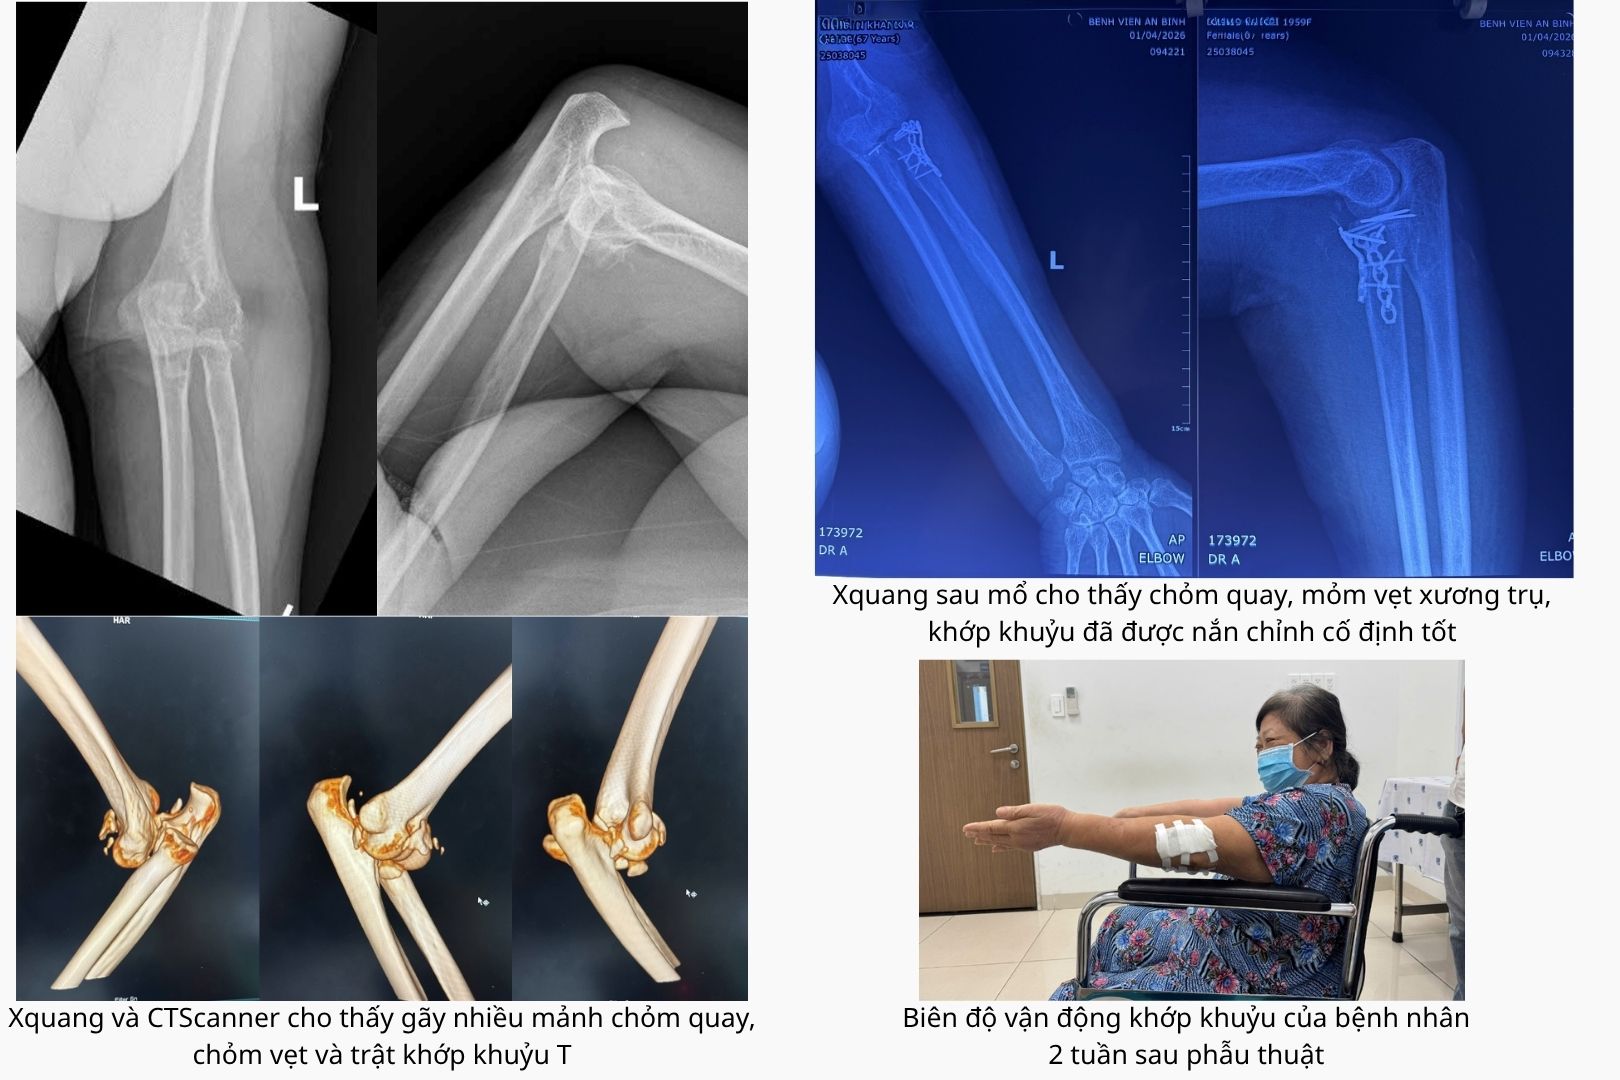

Trường hợp thứ nhất là bệnh nhân bị “tam chứng đau khổ” ở khuỷu tay gồm gãy mỏm vẹt xương trụ, gãy chỏm xương quay và trật khớp khuỷu. Bệnh nhân đồng thời mắc nhiều bệnh lý nền như tăng huyết áp, đái tháo đường, loãng xương và Cushing, khiến quá trình điều trị trở nên phức tạp.

Ê-kíp phẫu thuật đã tiến hành kết hợp xương quay bằng nẹp vít, cố định mỏm vẹt xương trụ bằng kim Kirschner và khâu phục hồi dây chằng bên ngoài. Sau can thiệp, khớp khuỷu được tái lập vững chắc.

Kết quả, sau 2 tuần phẫu thuật, vết mổ của cả hai bệnh nhân liền tốt, biên độ vận động khớp khuỷu phục hồi đáng kể.